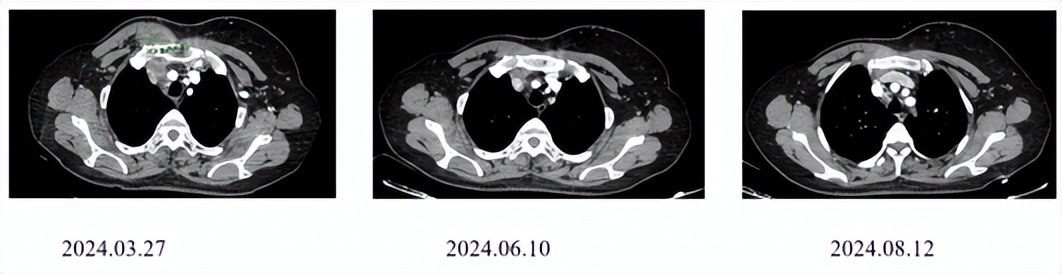

CT评估(右侧锁骨上区淋巴结):

CT评估(右胸壁):

二线治疗4周期后临床查体CR。

该病例为47岁的HER2+晚期乳腺癌患者,右乳癌术后辅助治疗(TCbH)3年后出现胸壁、区域淋巴结及骨转移。一线接受THP方案治疗约6个月后即出现局部进展,提示原发耐药。自2024年9月起,二线换用T-DXd进行治疗。疗效显著,治疗4周期后临床查体即达到CR,影像学评估显示病灶持续显著缩小。截至2025年9月异地就医前,患者持续处于“临近CR”状态,且安全性良好,未发生间质性肺病等严重不良反应。该病例成功印证了T-DXd对于THP治疗失败后的HER2阳性晚期乳腺癌患者,能够提供强效、深度且持久的疾病控制。